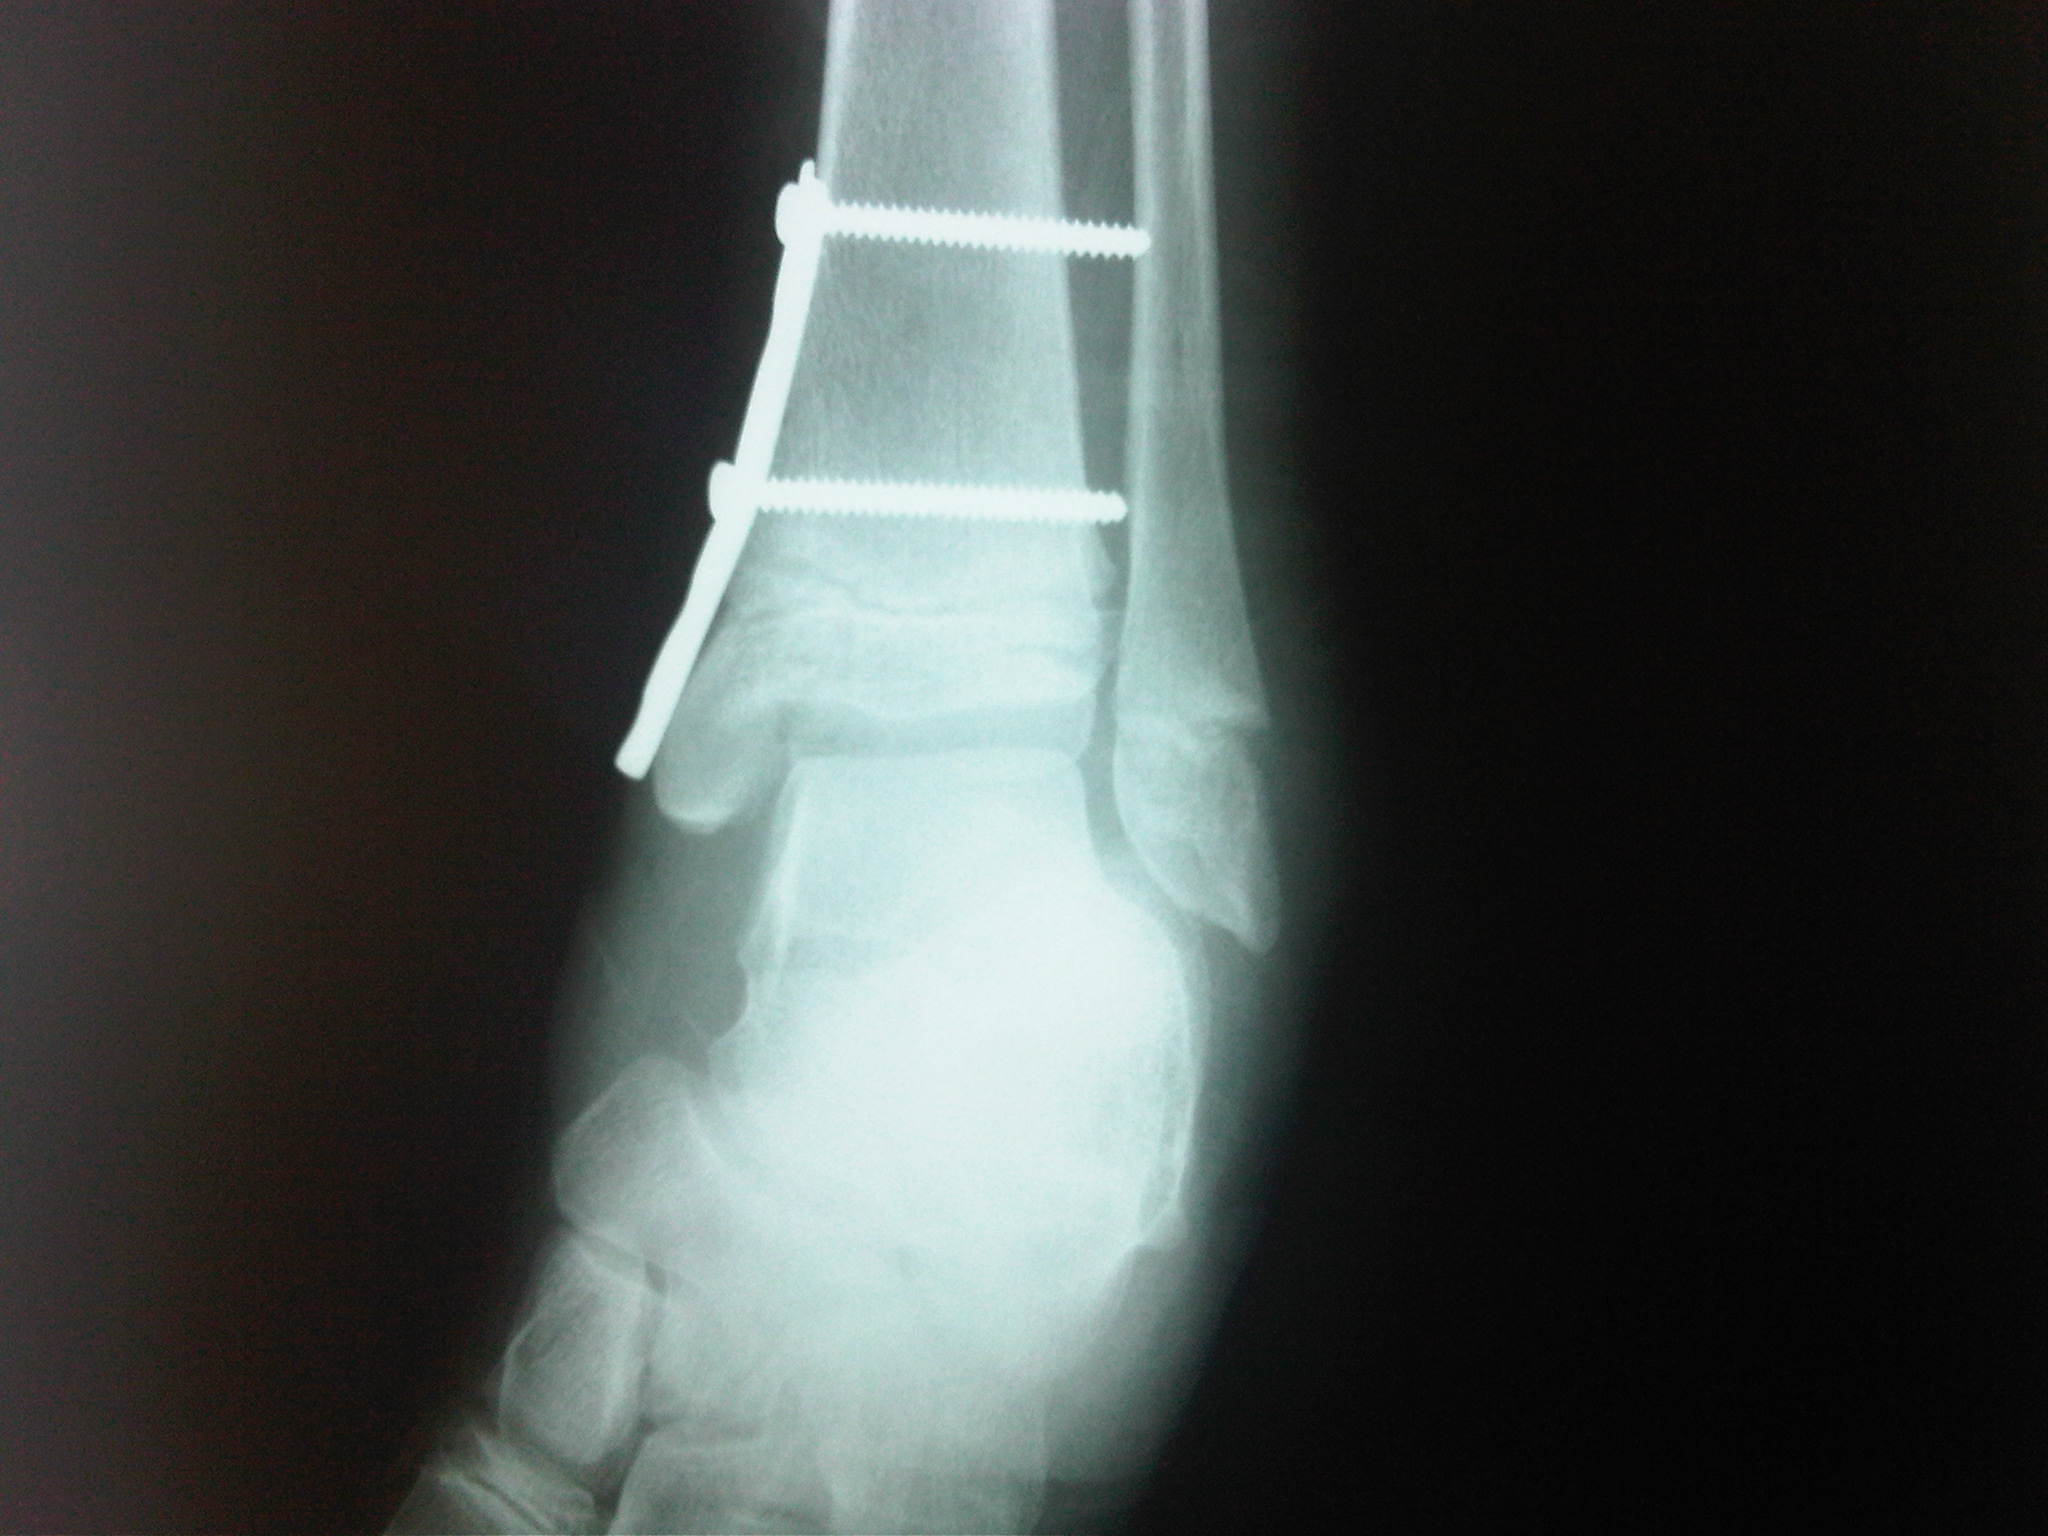

• 3. Luxofracturas de Tobillo y Pie.

• 5. Desarrollo de implantes en cirugía de pie y tobillo.